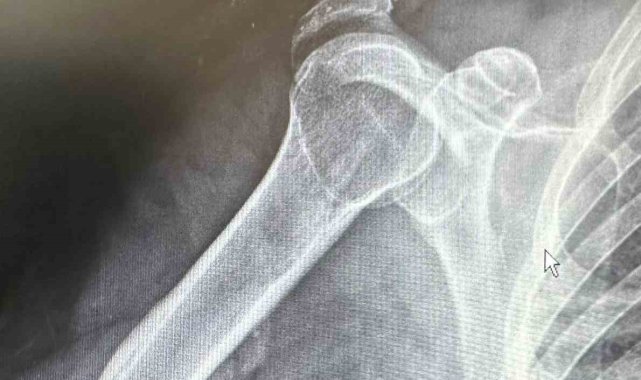

Batman'da, tenis oynarken omuz çıkığı yaşayan 64 yaşındaki Mehmet Şerif Rençber, ileri yaş nedeniyle ameliyat olamayacağı, kendiliğinden iyileşeceği cevabı olmasına rağmen başka bir doktorun özel plak kullanarak ameliyat etmesiyle sağlığına kavuştu.64 yaşındaki Mehmet Şerif Rençber, tenis oynarken omzunun üzerine düşmesiyle çıkık yaşandı. Rençber, tedavi için gittiği başka doktorlardan ileri yaşı nedeniyle ameliyat edilemeyeceği, kendiliğinde iyileşmesi gerektiği cevabını aldı. Batman Eğitim ve Araştırma Hastanesi Ortopedi ve Travmatoloji Uzmanı Dr. Mehmet Yavuz Başer'e başvuran Rençber, burada kullanılan özel plakla sağlığına kavuştu.Dr. Başer, hastanın 64 yaşında omuz çıkığı nedeniyle kendilerine başvurduğunu söyledi. Kendisi, arkadaşlarıyla tenis oynarken omuz üzerine düşme sonrası omuzunda bir çıkık geliştiğini belirten Başer, "Normalde bu omuz çıkığını genç hasta grubunda görebiliyoruz. Hastamız ileri yaş olmasına rağmen aktif spor yapan bir hastamız. Bize başvurduğunda omuz eklemi yerinde değildi. Hastanın kemik yapısına tam uyumlu, nadir kullanılan özel bir plak ile başarılı bir ameliyat gerçekleştirdik. Daha sonra biz de ameliyat kararı verdik. Ameliyatında daha çok gençlerde kullanılan nadir, özel şekilli, çengel bir plak kullandık. Daha sonra filmlerini de çekip kontrol ettikten sonra hastamızın ameliyatını başarılı bir şekilde tamamladık. Başarılı ameliyatın ardından hemen fizik tedavi sürecini başlattık. Hastamız bugünden itibaren yavaş yavaş omuz hareketlerini yapabilecek hale geldi. Kol askısından bir an önce kurtulacak ve hastamız en geç 2-3 haftaya kadar eski omuz hareketlerine ağrısız kavuşmasını bekliyoruz" dedi.Daha önce başvurduğu doktorların ileri yaşı nedeniyle ameliyatın mümkün olmayacağını ve kendiliğinden iyileşmesi gerektiğini söylediklerini belirten Rençber ise, "Benim gibi emekli olan arkadaşlarımla tenis oynarken omuz üstüne düştüm. Düşmem münasebetiyle omuzdaki açılma çok büyüktü. Birkaç doktora gittim ve Bu ameliyatın mümkün olamayacağını, 25 yaşına kadar olan hastaları genelde ameliyat yaptıklarını söylediler. 'Yaşının ileri yaş grubunda olduğunuz için dokunmuyoruz. O kendi kendine iyileşir' dediler. Sonra da Doktor Mehmet Yavuz Bey'e geldim. Mehmet Yavuz Bey durumu inceledi. Dedi ki, 'yapabilirim.' Bunda inşallah sıkıntı yaşamasın dedi şimdi başarılı bir ameliyat oldum, çok memnun kaldım. Bayağı ilgilendi. Ameliyat sonrası en ufak bir sancı, bir sıkıntı görmedim ve yaşamadım. Ameliyat sonrası bile omuzum neredeyse eskisi gibi hareket edebiliyorum, kısıtlılığım ilk gün bile ciddi şekilde azaldı" şeklinde konuştu.

Tenis oynarken omuz çıkığı yaşayan 64 yaşındaki hasta, kullanılan özel plakla sağlığına kavuştu

Batman'da, tenis oynarken omuz çıkığı yaşayan 64 yaşındaki Mehmet Şerif Rençber, ileri yaş nedeniyle ameliyat olamayacağı, kendiliğinden iyileşeceği cevabı olmasına rağmen başka bir doktorun özel plak kullanarak ameliyat etmesiyle sağlığına kavuştu.